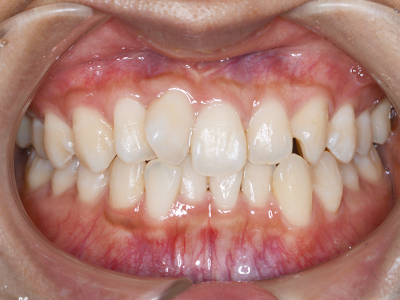

歯並びの相談に来られるお子様は、口呼吸をしているケースが多く、これが歯並びに大きな影響を与えています。

- 口呼吸をしている

↓ - 舌の位置が悪くなる

↓ - 頬の圧力が上の歯列にかかりやすくなる

↓ - 上あごが狭くなる

↓ - 下あごが狭くなる・下あごの位置が悪くなる

↓ - さまざまな不正咬合が生じる

ないき歯科クリニックでは、上あごの成長不足を補い、鼻呼吸を獲得しつつ歯列を整え、将来のお口をより健康な状態にすることをゴールに定める矯正治療をおこなっています。